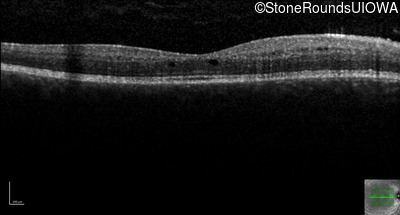

Optical Coherence Tomography - Left - 20/20 -1

Exemplar / OCT Stack